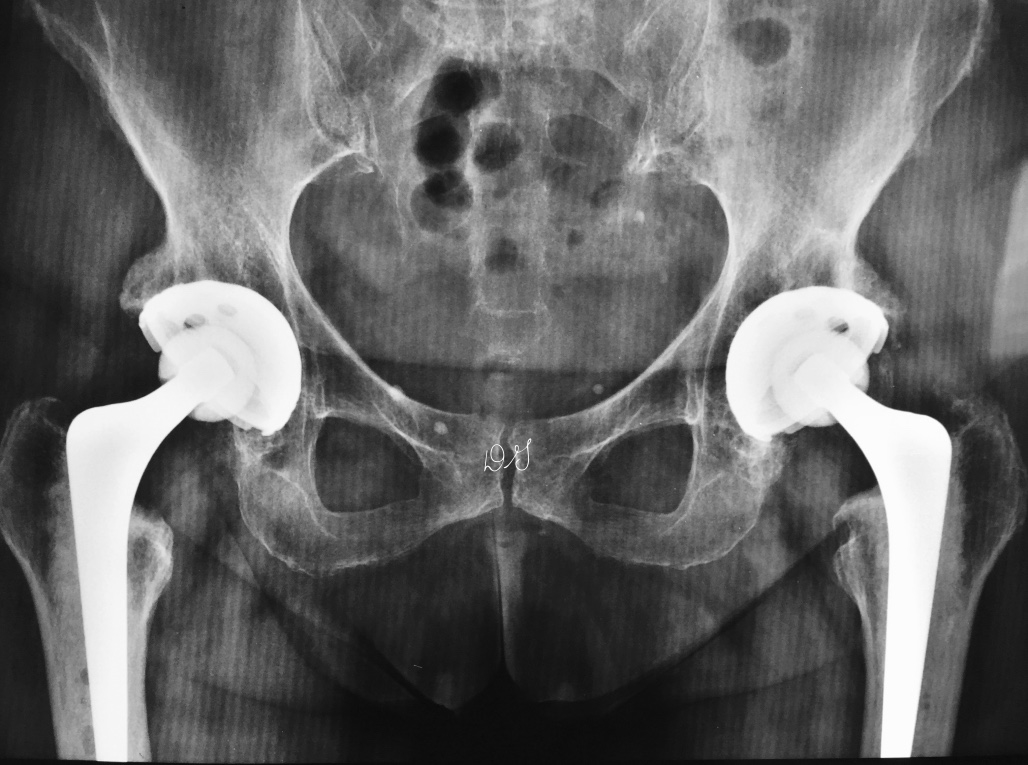

- Cirurgia em ambos os lados no meio do ano -

Artroplastia total de Quadril Exeter - Híbrida - Cerâmica - Polietileno high-cross-linked [/caption]